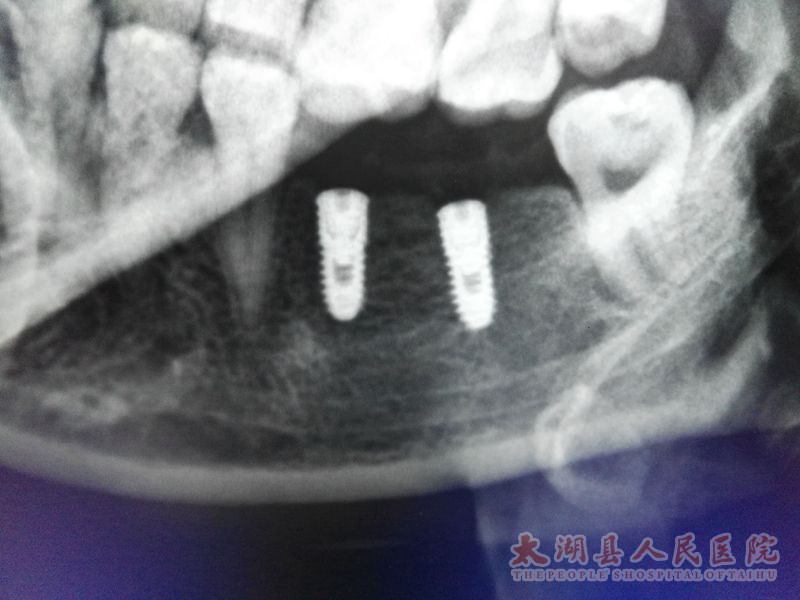

口腔科成功开展种植牙新技术

41日,县医院口腔科在安徽省种植专家的指导下成功为两例牙体缺失患者植入种植体四枚,术后效果理想。种植手术的成功开展填补了县医院种植技术的空白,标志着口腔科在修复牙列缺失技术方面得到了重大突破。